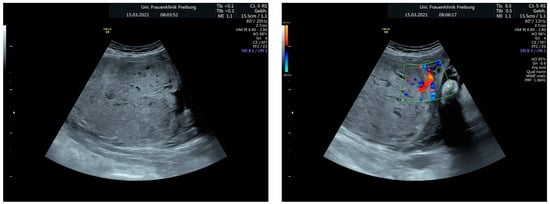

Sonographic findings (Figure 4):

Figure 4.

shows suspected placenta increta with dehiscence in the area of scar tissue from the previous uterotomy.

Intraoperative findings (Figure 5):

Figure 5.

Reveal placenta previa with placenta increta. The earlier suspected dehiscence was confirmed.